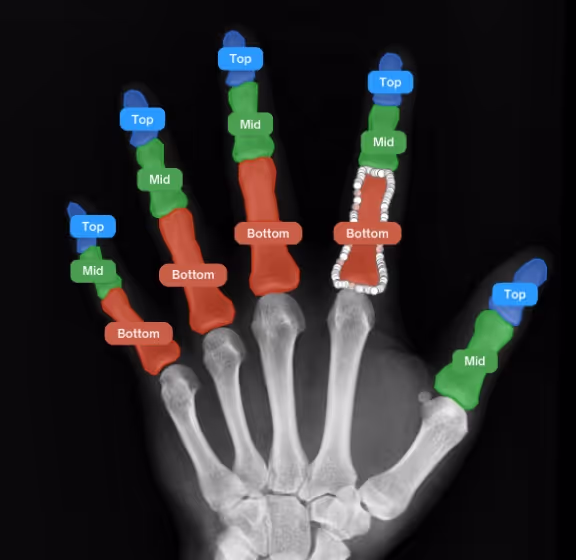

Bone Structural Diagnosis

X-Ray image analysis to identify normal and abnormal structures, diagnosis of diseases and prediction of treatment outcomes through AI.